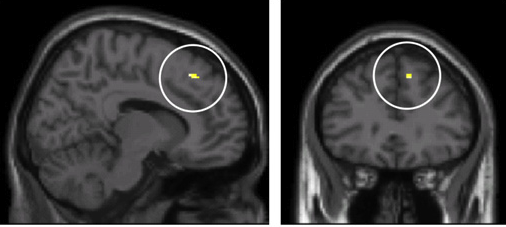

C’est quand on voit tout le monde faire un truc et qu’on veut faire pareil. C’est pour ça que la mode fonctionne. Cet effet de Panurge, ce besoin d’imiter nos semblables a même été observé dans nos cerveaux. Dans les cercles de la photo ci-après, c’est le cortex cingulaire antérieur, une zone spécialisée dans la détection d’erreur. Lorsqu’on s’aperçoit que notre jugement personnel ou notre comportement diffère de celui de la majorité, notre cortex cingulaire antérieur panique et nous incite à suivre la tendance.